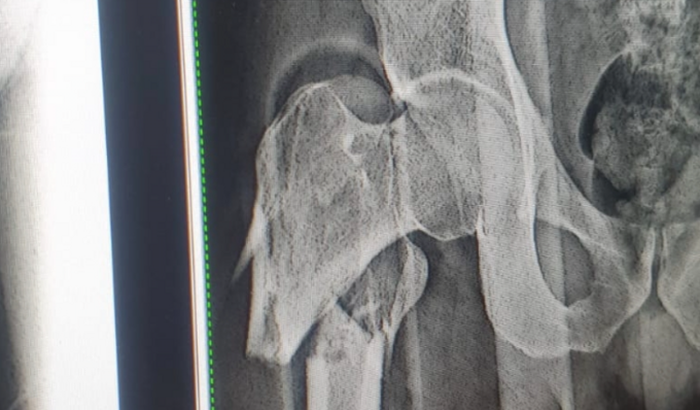

Graça e Paz! Me chamo Weber Teodoro Teixeira, e hoje, dia 28 de setembro, caí de uma altura de 4 metros e nesse acidente, tive uma fratura da cabeça do fêmur, no dedo da mão direita e na face. Estava fazendo um trabalho em uma oficina na cidade de Ji-Paraná/RO. Em decorrência desse acidente, eu preciso fazer uma cirurgia no valor de R$ 15.000,00 reais, a qual eu poderia fazer pelo SUS, porém, a previsão é de 21 dias para realizá-la e estou sentido muita dor, sem possibilidade de me movimentar. Agradeço a quem puder contribuir com qualquer valor ou compartilhar o link de contribuição em suas redes sociais. Que Deus retribua em dobro a você; peço toda benção dEle sobre a sua vida!